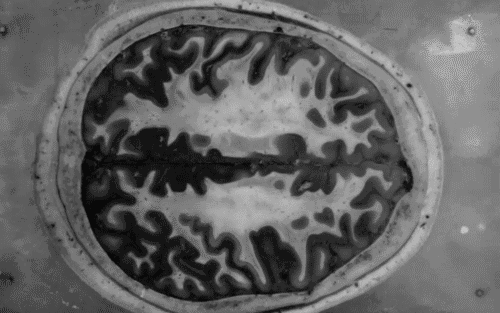

Éñ¾­ÏµÍ³µÄËðÉ˻ᵼÖÂÒ»Á¬´®µÄʼþ£¬×îÖÕ»áÔì³ÉÉñ¾­Ôª¶ªÊ§ºÍ¼±ÐÔ»òÂýÐÔ¹¦ÄÜÕϰ­¡£ÕâЩ¹ý³Ì¿ÉÒÔÒýÆðÉñ¾­ÏµÍ³¼²²¡È缡ήËõÐÔ¼¹Ëè²àË÷Ó²»¯Ö¢£¬ÅÁ½ðÉ­²¡£¬°¢¶û´Äº£Ä¬²¡£¬¶à·¢ÐÔÓ²»¯Ö¢£¬Öз磬´´ÉËÐÔÄÔËðÉË£¬¼¹ËèËðÉ˺ÍÄÔ̱µÈ¡£